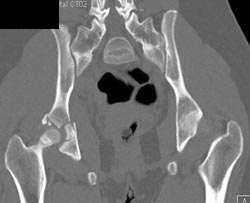

Acetabular Fracture